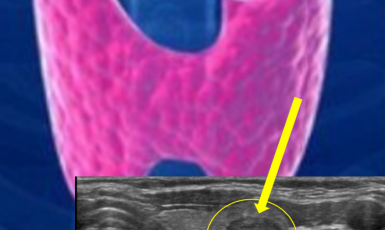

309번째 갑상선암 진단사례 (2019년8월30일) 목에 단단한 멍울이 만져지고 지속적으로 원인모를 불편한 증상이 지속되어 진료위해 내원한 환자분이셨습니다. 진찰상 앞쪽 ..

작성자 레이디유 작성일 09-24 조회 5